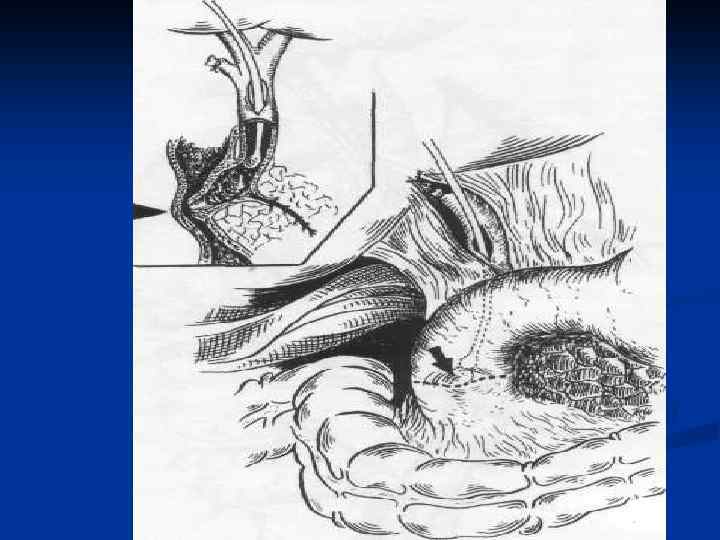

I. Восстановительные операции (восстановление проходимости протоков) 1. Эндобилиарные вмешательства под УЗИ или R – контролем (бужирование, баллонная дилатация, стентирование протоков). 2. Пластика стриктуры 3. Иссечение стриктуры с наложением анастомоза. II. Реконструктивные операции (наложение билиодигестивных анастомозов) 1. Анастомозы внепеченочных желчных протоков: а) с двенадцатиперстной кишкой (ХДА) б) с тощей кишкой (гепатико-, холедохоеюноанастомозы по Ру или по Брауну). 2. Анастомозы внутрипеченочных желчных протоков с сегментом тощей кишки, выключенной по Ру или желудком при высоких стриктурах

I. Восстановительные операции (восстановление проходимости протоков) 1. Эндобилиарные вмешательства под УЗИ или R – контролем (бужирование, баллонная дилатация, стентирование протоков). 2. Пластика стриктуры 3. Иссечение стриктуры с наложением анастомоза. II. Реконструктивные операции (наложение билиодигестивных анастомозов) 1. Анастомозы внепеченочных желчных протоков: а) с двенадцатиперстной кишкой (ХДА) б) с тощей кишкой (гепатико-, холедохоеюноанастомозы по Ру или по Брауну). 2. Анастомозы внутрипеченочных желчных протоков с сегментом тощей кишки, выключенной по Ру или желудком при высоких стриктурах